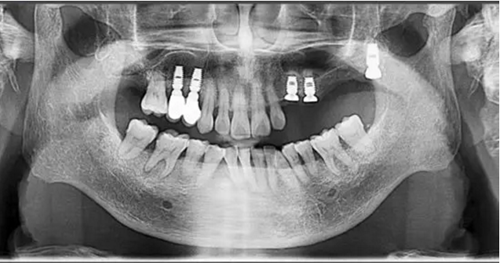

術(shù)后當(dāng)天 術(shù)后7個月

術(shù)后8個月 術(shù)后10個月

術(shù)后13個月

術(shù)后14個月